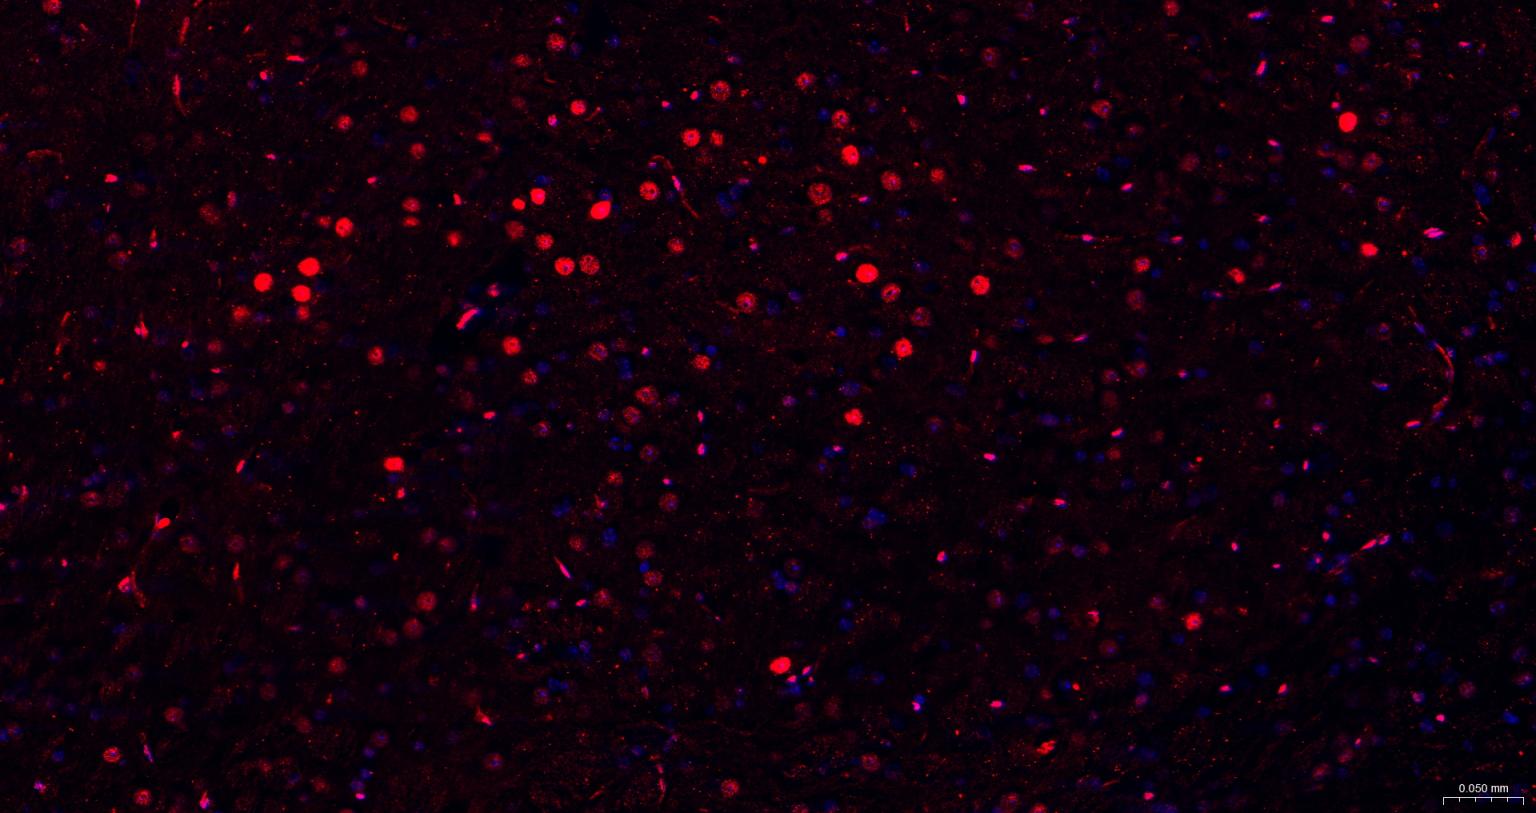

Paraformaldehyde-fixed, paraffin embedded Mouse Cerebrum; Antigen retrieval by boiling in sodium citrate buffer (pH6.0) for 15 min; The section was incubated with Oct-1 Monoclonal Antibody, Unconjugated (bsm-63240R) at 1:200 overnight at 4°C. Followed by conjugated Goat Anti-Rabbit IgG antibody (Red, bs-0295G-BF594), DAPI (blue, C02-04002) was used to stain the cell nuclei.

Paraformaldehyde-fixed, paraffin embedded Rat Cerebrum; Antigen retrieval by boiling in sodium citrate buffer (pH6.0) for 15 min; The section was incubated with Oct-1 Monoclonal Antibody, Unconjugated (bsm-63240R) at 1:200 overnight at 4°C. Followed by conjugated Goat Anti-Rabbit IgG antibody (Red, bs-0295G-BF594), DAPI (blue, C02-04002) was used to stain the cell nuclei.